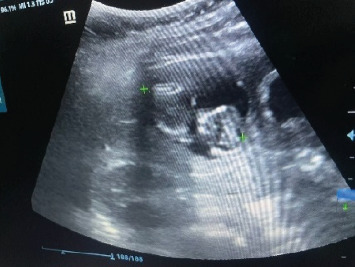

简介:原发性肝异位妊娠罕见;据报道,每次子宫妊娠的发病率约为1:15 000。本研究旨在探讨肝异位妊娠的临床表现及治疗方法。病例介绍:我们提出的情况下,病人没有怀孕史谁提出腹痛难治性治疗。人绒毛膜促性腺激素(β-hCG)水平为55,710 mIU/mL,腹部超声显示右肝叶水平出现50 mm × 50 mm的圆形图像,并发低血容量性休克。在诊断为腹部异位妊娠的情况下,患者接受了手术。讨论:最初,进行了剖腹探查,发现存在出血、凝块和妊娠囊;随后,进行楔形切除,Pringle手法和肝脏填塞,在患者的病例中获得了良好的结果。结论:原发性肝性异位妊娠可通过β-hCG测定和连续腹部超声检查诊断。治疗可以是药物(甲氨蝶呤)或手术,应用技术,如品客手法。

Introduction: Primary hepatic ectopic pregnancy is rare; it has been reported to have an incidence of 1:15,000 per uterine pregnancy approximately. This study aims to determine the clinical presentation and treatment of hepatic ectopic pregnancy. Presentation of Case: We present the case of a patient with no history of pregnancy who presented with abdominal pain refractory to treatment. With a human chorionic gonadotropin hormone (β-hCG) measure of 55,710 mIU/mL, an abdominal ultrasound that revealed the presence of a rounded image of 50 mm × 50 mm at the level of the right hepatic lobe and the complication of hypovolemic shock. Under the diagnosis of an abdominal ectopic pregnancy, the patient underwent surgery. Discussion: Initially, an exploratory laparotomy was performed, which revealed the presence of bleeding, clots, and a gestational sac; subsequently, a wedge resection was done, and a Pringle maneuver and hepatic packing were performed, obtaining favorable results in the patient's case. Conclusion: The diagnosis of primary hepatic ectopic pregnancy is made through β-hCG measurement and serial abdominal ultrasonography. Treatment can be pharmacological (methotrexate) or surgical, applying techniques such as the Pringle maneuver.